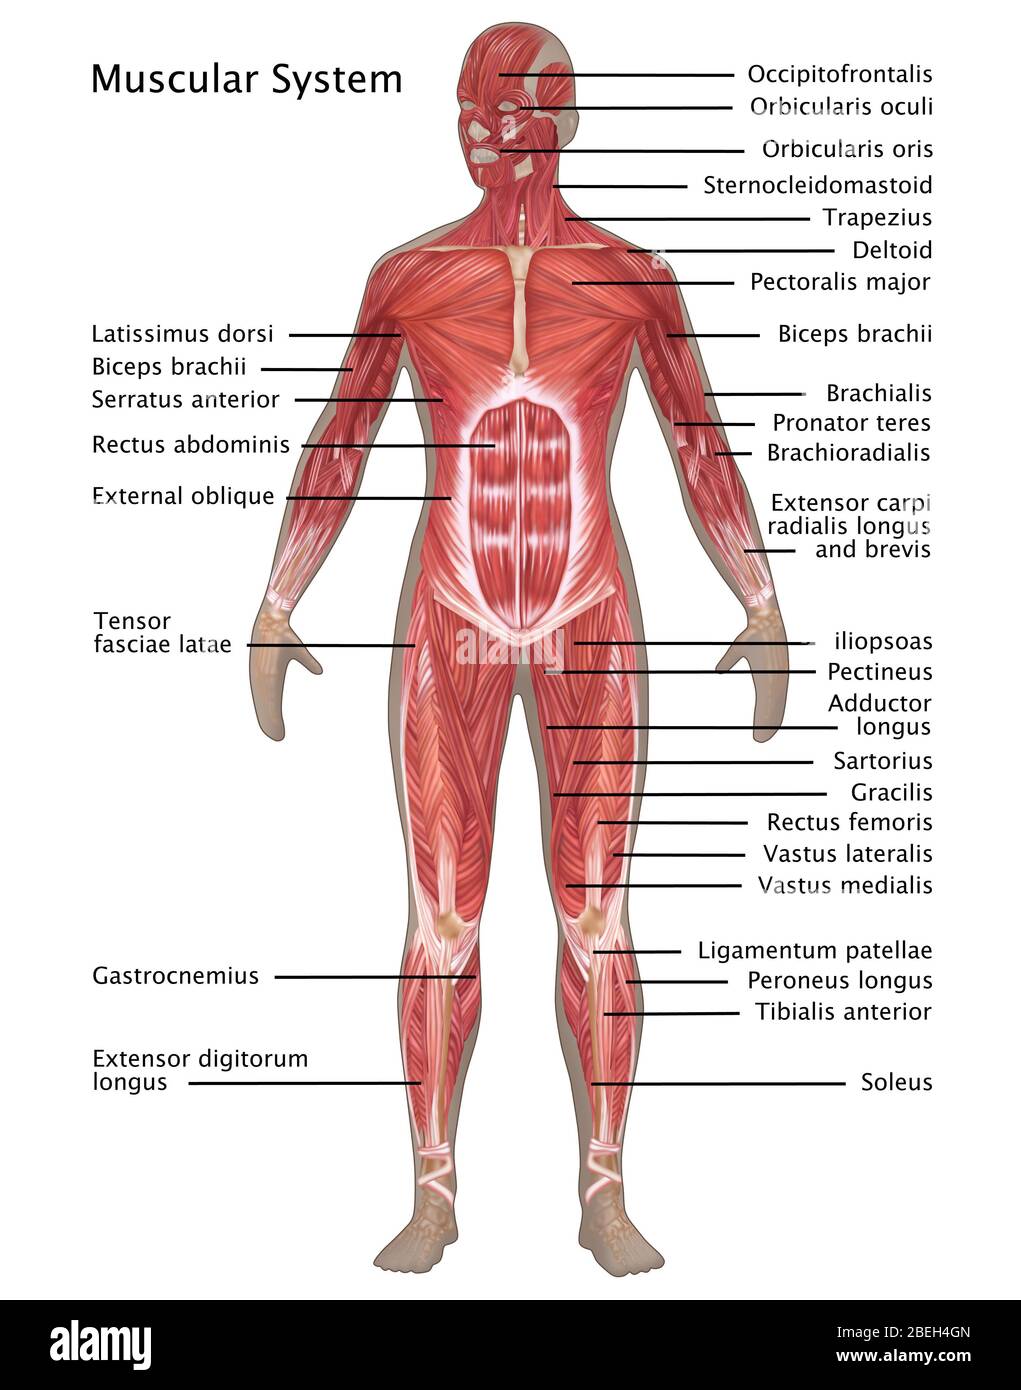

Muscular System in Female Anatomy Stock Photohttps://www.alamy.com/image-license-details/?v=1https://www.alamy.com/muscular-system-in-female-anatomy-image353189333.html

Muscular System in Female Anatomy Stock Photohttps://www.alamy.com/image-license-details/?v=1https://www.alamy.com/muscular-system-in-female-anatomy-image353189333.htmlRF2BEH4GN–Muscular System in Female Anatomy